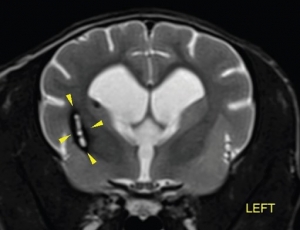

✎ 圖四及圖五腦部微出血在MRI特殊序列下無所遁形!

- MRI 是診斷黃金工具:能清楚觀察缺血/出血位置與範圍,一些特殊序列如加權梯度回波序列(T2*W、GRE)、擴散加權成像(DWI)等對出血及缺血性病灶極具診斷力